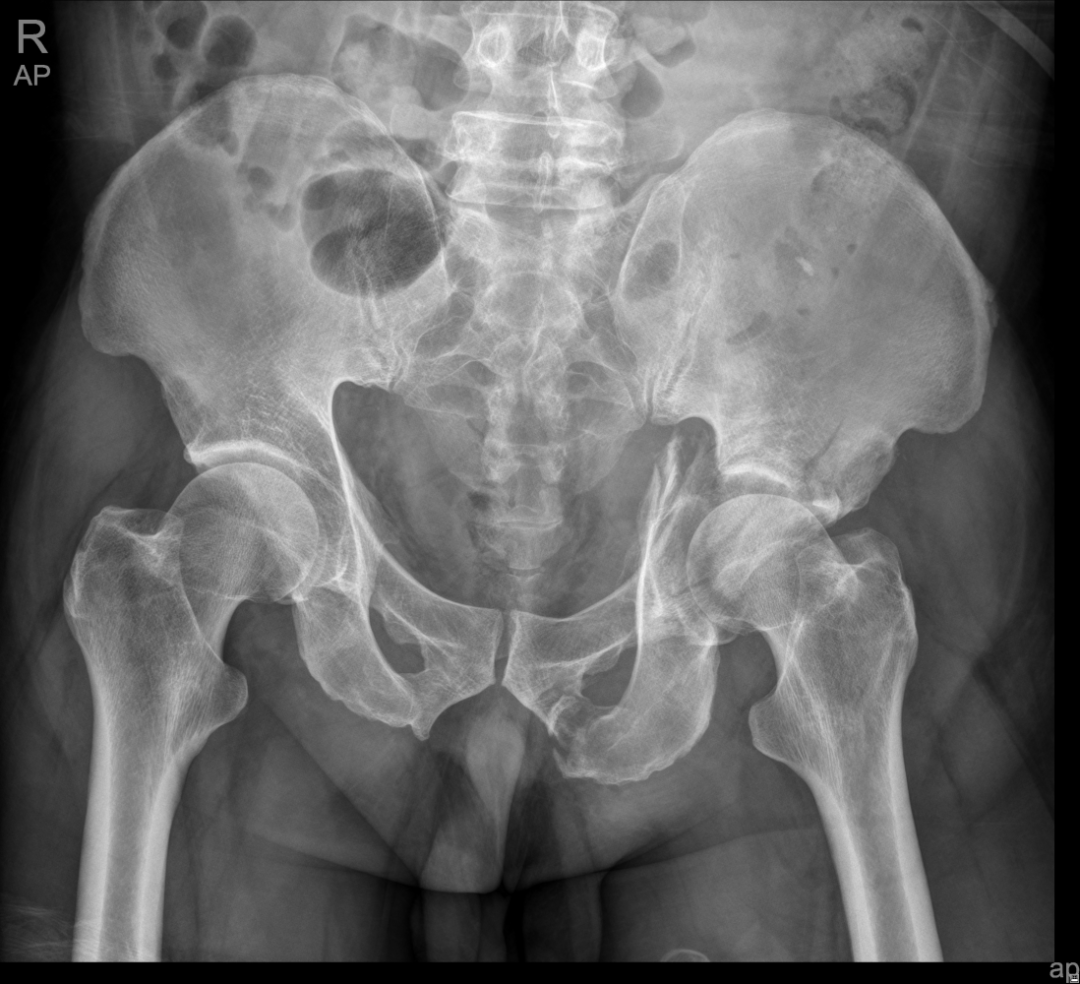

The acetabular fracture, known as “the Pearl of the Crown” of traumatic orthopedics, is the most difficult problem to handle. Only when the surgery is done meticulously, can targeted treatment be achieved. Therefore, if doctors in a hospital are capable to perform such a complex surgery for treating acetabular fracture, it reflects that the hospital’s medical level in trauma emergency and orthopedics is relatively high.

In April this year, the Traumatic Orthopedics Center of the Shenzhen Second People’s Hospital performed its first internal fixation surgery by combining the pararectus approach with K-L approach for acetabular fracture. This surgical technique is a new anterior surgical approach that is popular at home and abroad in recent years. It can guarantee the acetabulum could be exposed directly through the incision and is less invasive than the ilioinguinal approach.  However, the incision is so close to the external iliac artery and the femoral nerve that it requires the surgeon to be familiar with the anatomical position and to have a high level of surgical technique. The pararectus approach is the most popular approach widely used for acetabular fractures surgery due to its advantages of less invasive and more targeted.

A hip fracture is a super serious injury, which is typically the result of a high-energy event. It can be caused by the surrounding fractures of the pubis, ischium or ilium, or by a central dislocation of the hip. Clinical symptoms of a hip fracture include local pain, swelling and bruising in and around the hip areas, for example, around the pudendum, groin or lumbar, and inability to get up from a fall or to walk, and shorter leg on the side your injured hip.